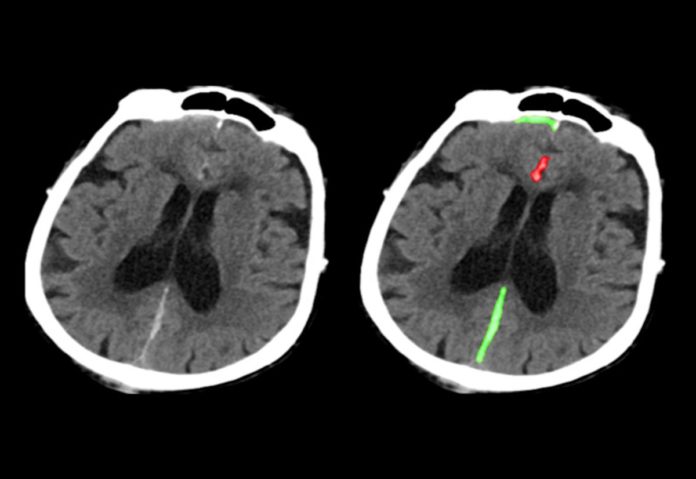

Il processo si basa sull’analisi di 4.396 scansioni CT. Questo è un numero relativamente piccolo di campioni, ma le anomalie sono state dettagliate “a livello di pixel”, secondo UCSF. In altre parole, l’intelligenza artificiale aveva molte meno probabilità di interpretare erroneamente il rumore e altri errori e individuare soltanto le vere emorragie. L’intelligenza artificiale viene addestrata a osservare una parte di un’immagine alla volta e non tutto l’insieme: questo tipo di osservazione ridurrebbe le possibilità di ipotesi errate.

Come altri sistemi di rilevamento basati sull’intelligenza artificiale, anche questo non sostituirà completamente i medici. Sarà invece di supporto: in pochi secondi può fornire un rapporto e può classificare automaticamente diversi tipi di emorragia, facendo risparmiare tempo prezioso ai medici in caso di emergenza e garantendo loro la possibilità di individuare emorragie difficilmente rintracciabili e che potrebbero essere fatali nelle peggiori circostanze.